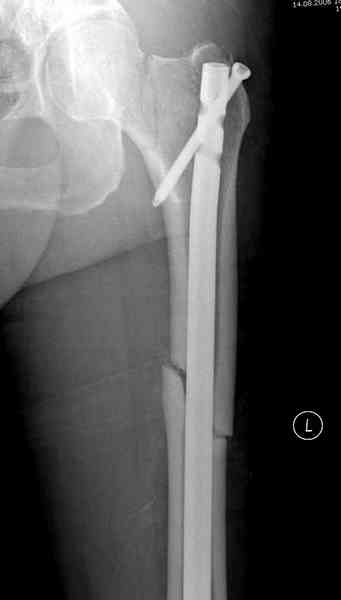

В первый же день произведено антеградное штифтованием DePuy Trochanteric Nail.

На второй день (7) обнаружен пропущенный перелом,

сделаны Компьютерная Томограмма

и проведены шурурпы через и спереди штифта без удаления.

Послеоперационные снимки